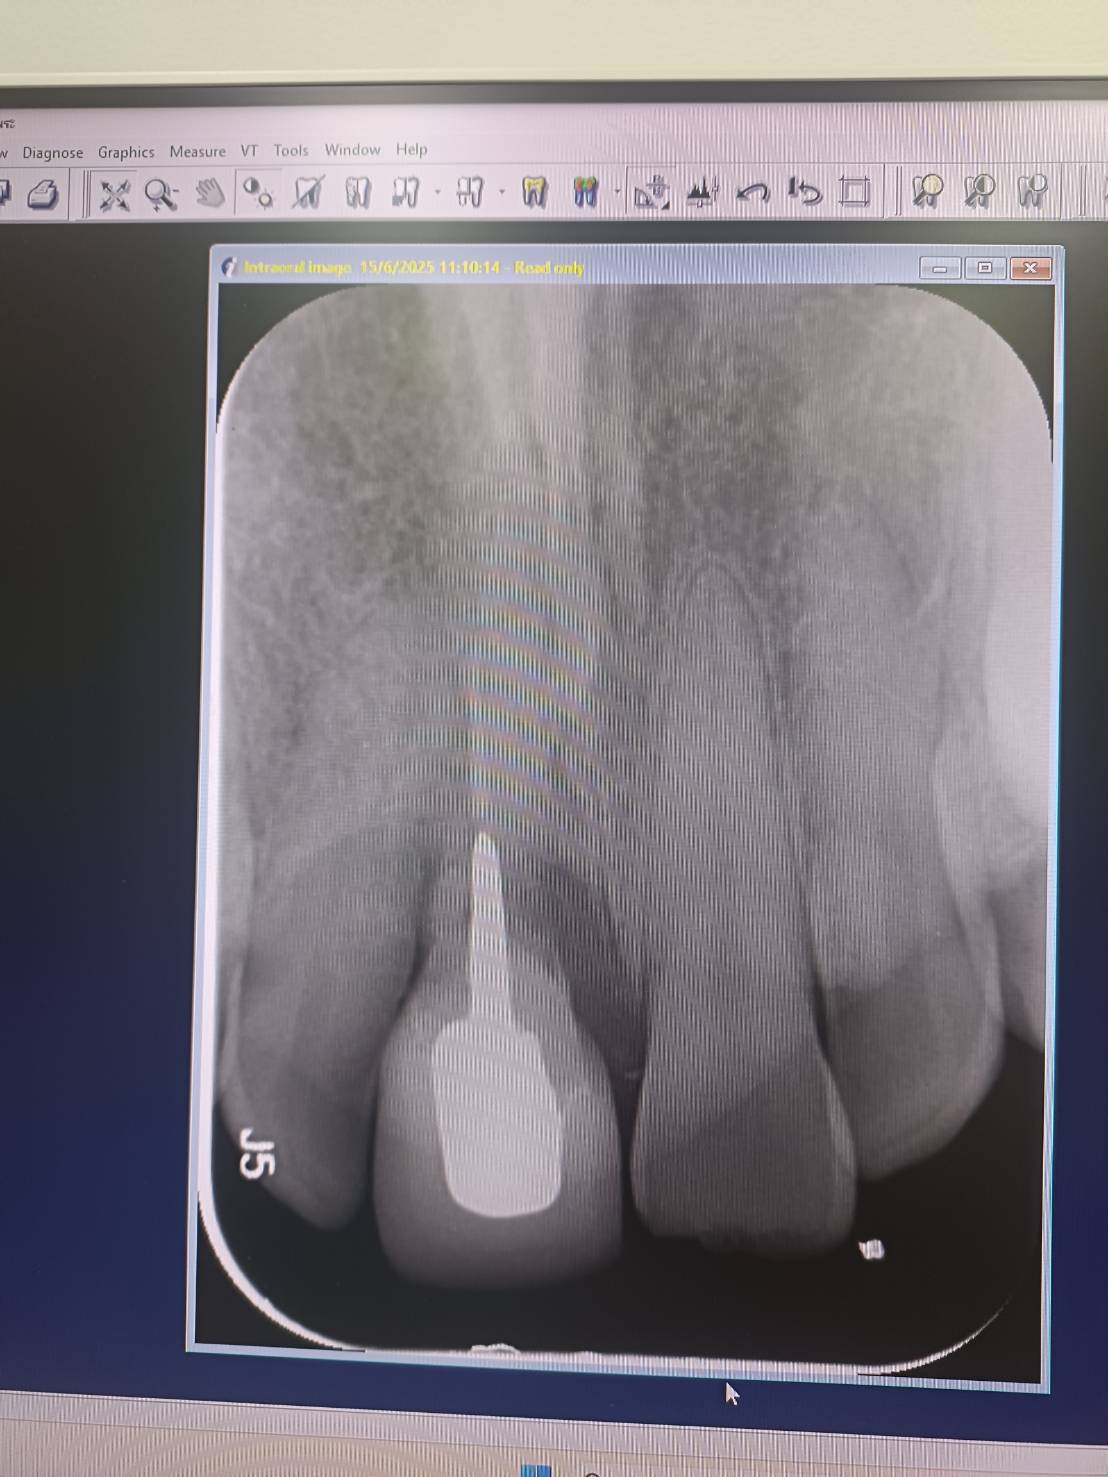

เมื่อประมาณ 5 ปีก่อน ผมได้ประสบอุบัติเหตุหนักทำให้สมองเสื่อม สมองกลับไปเป็นเด็กอีกครั้ง และฟันหน้าหัก และได้เข้ารับการรักษาที่รพ.ราชวิถี ตรงอนุสาวรีย์ชัยฯ กทม. แพทย์ได้ทำการรักษารากฟัน โดยจ่ายเป็นเงินทั้งสิ้น 30,000 บาท หลังจากนั้นเพียง 3 ปี ฟันปลอมซี่นั้นได้เกิดโยก และสุดท้ายได้ทำการถอนทิ้ง โดยจากฟิล์มเอ็กซเรย์ ทันตแพทย์ส่วนมาก ได้บอกตรงกันว่า "เนื้อฟันได้ถูกกรอทิ้งไปค่อนข้างเยอะ" ระยะ 3 ปี กรดของน้ำลายไม่สามารถกัดกล่อนไปได้มากขนาดนั้น จึงระบุได้ว่าเป็นการกระทำที่ไม่ชอบธรรมโดยเจตนาของทันตแพทย์ผู้รักษา เหตุเนื่องด้วย ตอนนั้น ประกันสังคมผมอยู่ที่รพ.ราชวิถี แต่ด้วยมีเหตุจำเป็นจึงย้ายรักษารพ.ที่ตวจ. หากผมยังอยู่ที่กทม.ผมไม่อาจทราบได้ว่าผมจะถูกทุจริตค่ารักษาพยาบาลไปอีกมากเท่าใด และ พอผมส่งเรื่องร้องเรียนให้กับทางรพ.ราชวิถี กลับไม่มีการรับผิดชอบต่อการกระทำของบุคคลากรของตน แม้แต่เพียงนิดเดียว (นิดเดียวก็ไม่มี) พร้อมกลับโดยตำหนิกลับด้วยถ้อยคำดูถูก "เห็นหน้าโง่ๆ กูจะหลอกกินตังมัน" เนื่องด้วยตอนนั้น ความจำเสื่อม และกลับไปเป็นเด็กอีกครั้ง เลยทำให้หน้าตาค่อนข้างจะซื่อบื่อ ดูหลอกง่ายครับ